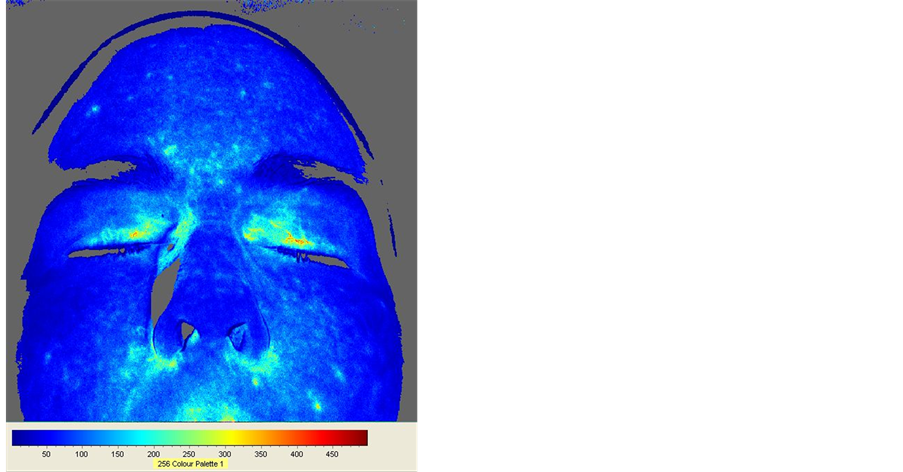

3.1.1. Subject A—Female, Caucasian, 33

Subject A came with an overall body pain level at 3 (on a scale from 1 to 10). Most of the entire neck/back/ arms/ forearms/thighs/legs dropped to a 1 level after one hour of grounding. Figure 1 shows two FBF images as recorded by the camera. The left image was taken at 11 minutes and 50 seconds (710 seconds, equivalent to frame 71, with each frame equal to 10 seconds) which corresponds to the end of the relaxation period. The right image was taken at 45 minutes and 10 seconds (2710 seconds, frame 271), corresponding to the highest mean FBF value of the highest peak after relaxation. Each time she moved her head, a dip in blood flow can be seen (movement artifact) in the top graph of Figure 2, which shows unprocessed mean FBF values (flux) over time. These dips are noted using blue arrows. The bottom graph of Figure 2 shows the same graph but corrected for artifacts and smoothed. Each dip was replaced using the method previously described and then smoothed. From Figure 2, it can be seen that mean FBF decreased for about 12 minutes (corresponding to the relaxation period), remained more or less stable for another 28 minutes (with periodic peaks and troughs) and started to increase after that. The peaks and troughs produce a rhythmic fluctuation in mean FBF with a periodicity of 4 minutes and 20 seconds (260 seconds, corresponding to 26 periods of 10 seconds, as noted in the figure) that started after the relaxation period.

Flux at 11 minutes 50 seconds (frame no 71) Flux at 45 minutes 10 seconds (frame no 271)

Figure 1. Subject A FBF images at 11 minutes and 50 seconds (left image) and 45 minutes and 10 seconds (right image). The flux intensity scale is shown below each image (dark blue = lowest flux; dark red = highest flux). There is a clear increase in FBF in the right image compared to the left image, especially around the eyes and the cheeks. Descriptive statistics for the left image: Mean Flux = 118.8; SD = 59.2; Flux min = 0; Flux max = 1129. Descriptive statistics for the right image: Mean Flux = 162.4; SD = 105.9; Flux min = 0; Flux max = 1053.